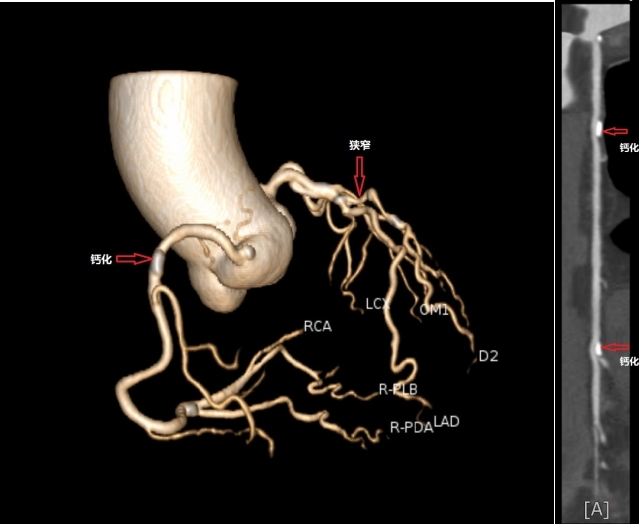

4. 冠脉CTA(CT血管成像)——“高清摄像头”直击血管内部

原理:打碘造影剂+高速CT扫描,三维重建你的冠状动脉。

优点:无创、图像清晰,能看到血管堵了多少、堵在哪。

缺点:部分设备对心率要求高(心律不齐可能“糊片”),碘过敏者慎用。

适合:有症状但不想做造影的人,或体检发现“可疑堵点”者。